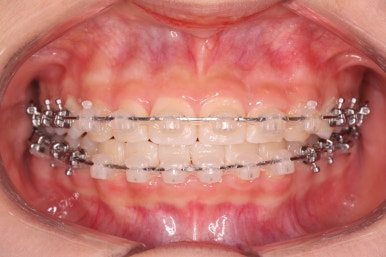

치료 종료 후의 모습입니다.

치아들이 가지런하게 되었고, 나오지 못하던 치아도 잘 나와서 가지런해졌습니다.

해당 부위 앞뒤로 쓰러져 있던 치아들도 축이 바로 잡혔고, 자연스레 위-아래 치아의 중앙선도 맞아졌습니다.

부산치아교정잘하는곳 키다리아저씨치과에서 이번 청소년 환자분께 치료하느라 소요된 기간은 총 16개월이였습니다.

이제 전후 비교입니다.

16개월만에 굉장히 좋아진 모습입니다.